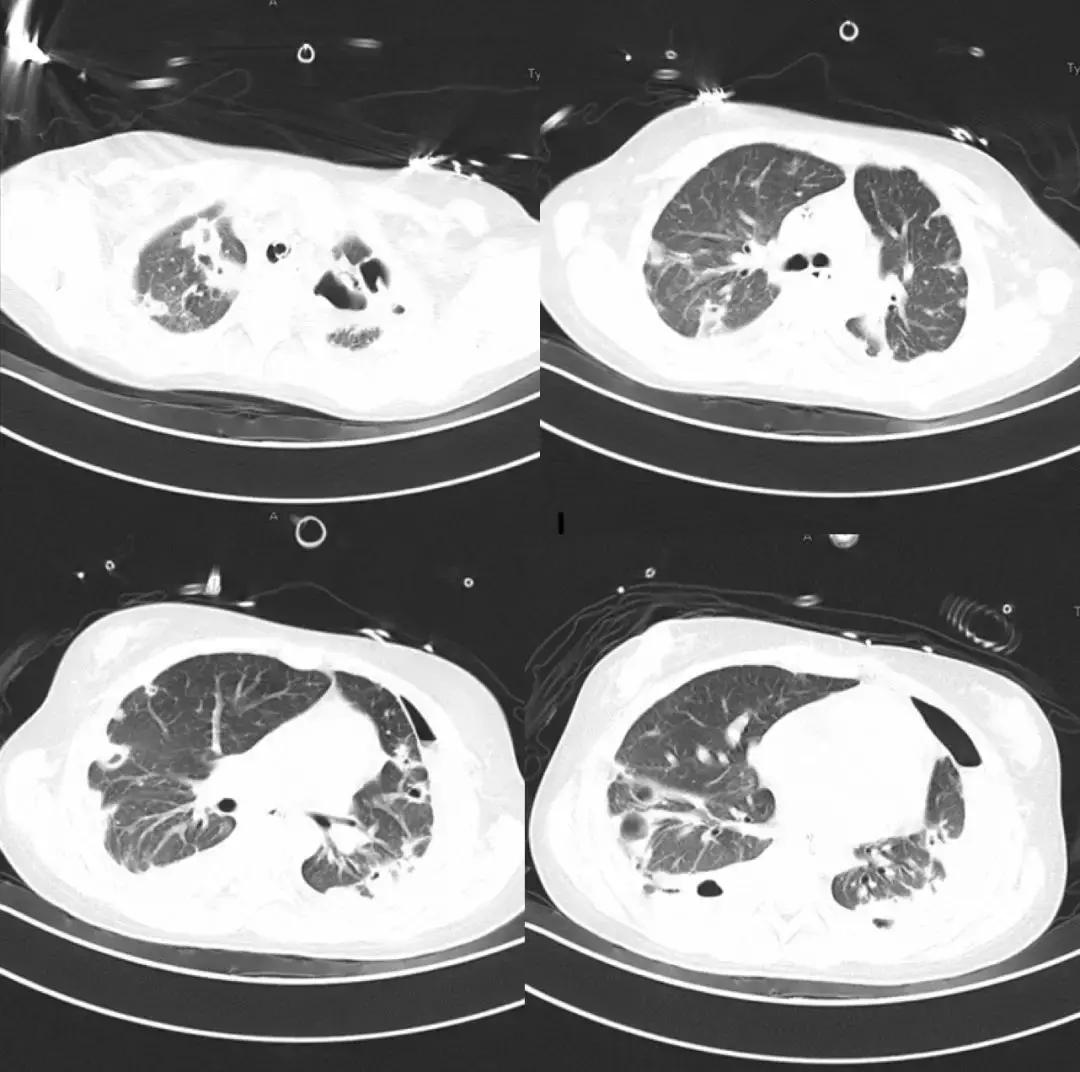

*影像学仍持续变化:

左侧胸腔病变为肺大泡?气胸?如何处理?药物是否需要调整?

*局部气胸引流

- 行左侧胸腔穿刺共两次,共抽出气体约2000ml;

- 患者呼吸困难缓解;

- 患者体温高峰逐渐下移;

- 复查血常规:白细胞9.79*10^9/L;降钙素原0.18ng/ml;血培养阴性

7月27日胸部CT

7月27日成功拔除气切插管;口服利奈唑胺序贯治疗;